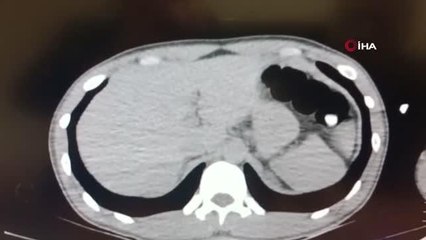

şüphelilerin emniyetten çıkışıbr -şüphelilerin hastaneye getirilmesibr -şüphelilerin adliyeye getirilmesibrbr( MUŞ ) MUŞ br br - Muş’ta narkotik polislerinin teknik takibe aldığı 2 şüpheli, midelerinde gizledikleri uyuşturucuyla kıskıvrak yakalandı.Muş İl Emniyet Müdürlüğü Narkotik Suçlarla Mücadele Şube Müdürlüğü görevlilerince uyuşturucu ve uyarıcı madde ticareti yapan şahıslara yönelik operasyonlar devam ediyor. 17 Şubat 2021 tarihinde 2 şüpheli şahıs otobüsten indikleri sırada polis ekipleri tarafından gözaltına alındı. Polis, üst araması yaptığı 2 kişide uyuşturucu maddeye rastlamazken, şüpheli ve tedirgin hareketleri sonucu şahıslar Muş Devlet Hastanesine götürülerek beden röntgeni kontrollerinden geçirildi. Kontrol sonrası vücut boşluğunda yabancı cisimlerin olduğu belirlenen şüphelilerin midesinden 5 parça halinde 69,39 gram eroin ile 10,03 gram metamfetamin maddesi ele geçirildi.Şüpheli şahıslar, çıkarıldıkları adli makamlarca tutuklandı.